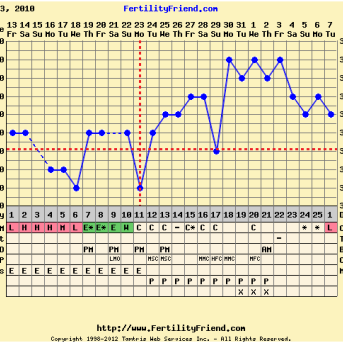

Uma das formas mais eficientes de detecção da ovulação é a temperatura basal. Essa técnica ajuda a identificar a ovulação através do comportamento da temperatura corporal em um estágio de repouso de pelo menos seis horas seguidas. A temperatura deve ser tirada sem qualquer movimento brusco da mulher. Quando temos um padrão de atividade da temperatura corporal, conseguimos detectar o padrão de ovulação daquela mulher. Normalmente a temperatura cai um ou dois dias antes da ovulação acontecer pela alta concentração de estrogênio e de LH.

O teste deve ser feito a partir do primeiro dia do período fértil, ou em mulheres desreguladas, assim que o muco ovulatório ou sintomas forem notados. Aliás, o muco é um forte indicio do inicio do período fértil. Ele tem duração aproximadamente de sete dias e pode ter o dia mais fértil por volta do quarto dia. Para mulheres que praticam o método da temperatura basal, o melhor dia de iniciar os testes seria no primeiro dia da queda da temperatura, pois o estrogênio provoca esta queda e sempre será sinal de que a ovulação está próxima. O melhor horário para fazer o teste seria à tarde, pois os hormônios estariam em um patamar equilibrado. Por volta das 16, 17 horas é um momento excelente!